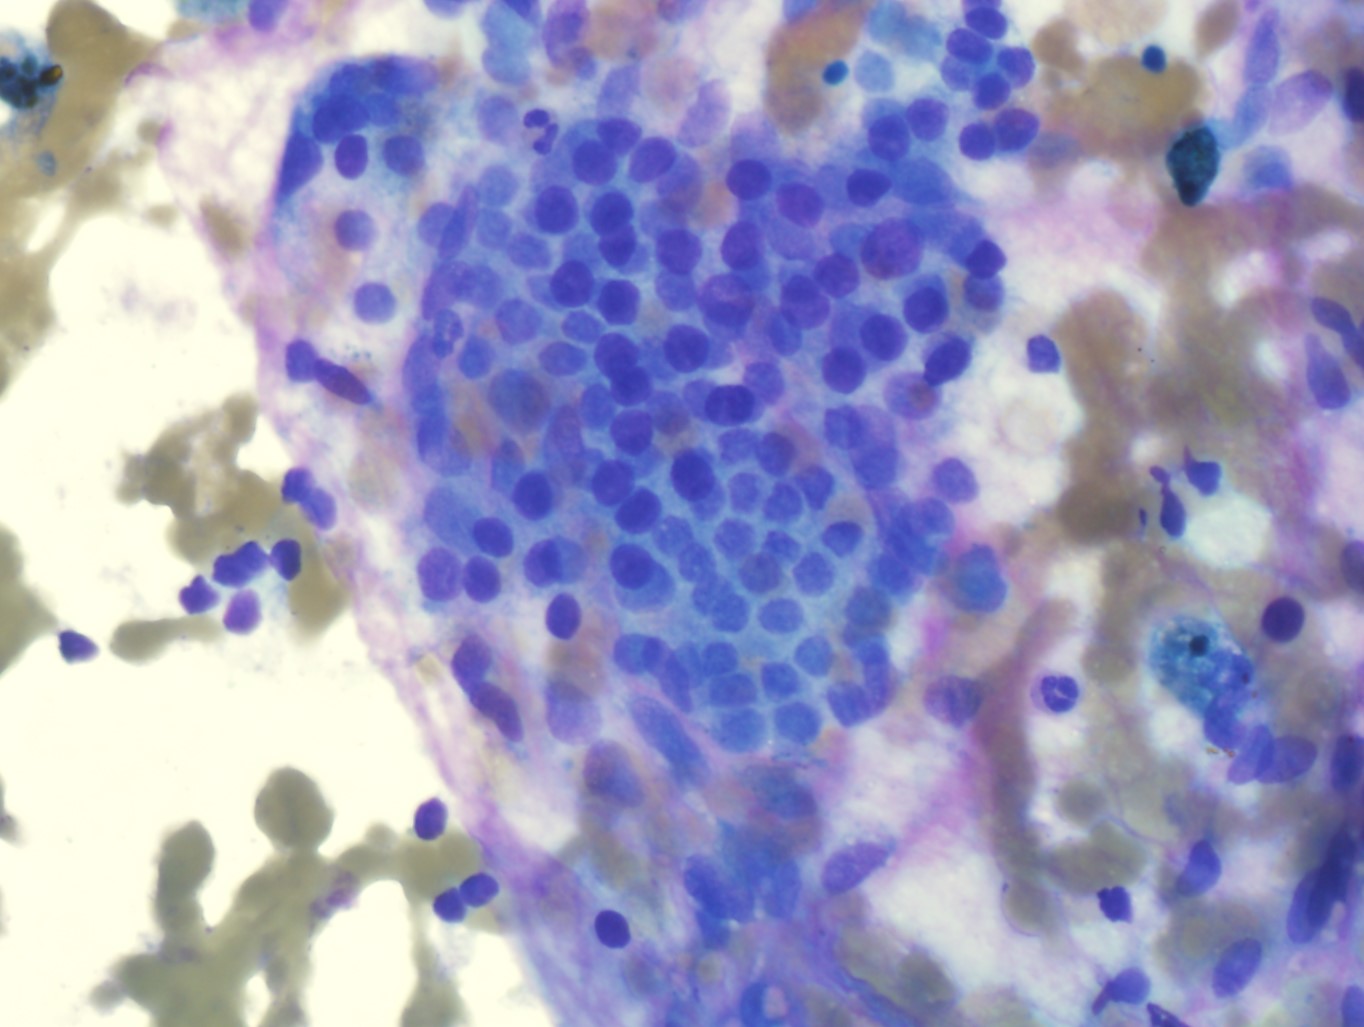

Picture149 yo with breast mass. Hx of breast implants and no cancer. CD45-/CD3-/CD20-/GATA3-/CK7-

What's the underlying...